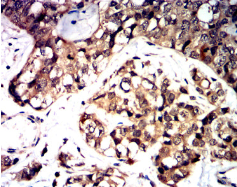

IHC    1/200 - 1/1000